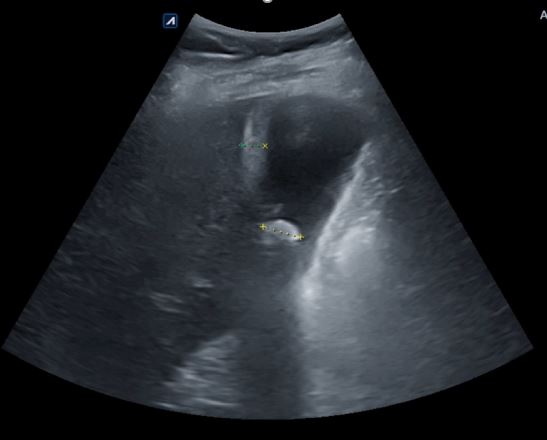

Ecoscopia abdominal: Vesícula biliar distendida con litiasis y barro biliar; visualizándose un engrosamiento de su pared. Murphy ecográfico negativo, compatible con colecistitis aguda litiásica.

Juicio clínico: Colecistitis aguda litiásica.